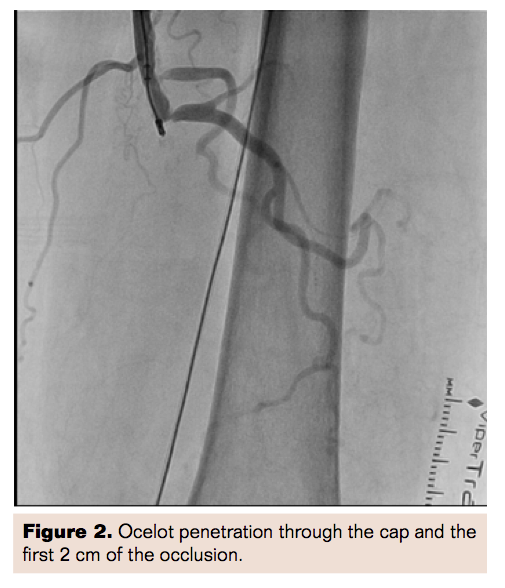

The Wildcat was easily advanced through the rest of the total occlusion along the SFA into the popliteal and proximal third the anterior tibial (AT) artery. The Wildcat catheter was removed, and the 0.035˝ wire was exchanged for a 0.014˝ Command guidewire (Abbott Vascular) using the Quick Cross catheter. The Command wire was easily advanced through the AT into the collateral to the posterior tibial (PT) artery in a retrograde fashion. The AT was ballooned using an Armada 2.5 mm x 200 mm x 150 cm balloon (Abbott Vascular). The balloon was removed and 0.014˝ Quick Cross catheter was used to traverse the plantar collaterals to the PT to attempt to open the occlusion in retrograde fashion, but the attempt was unsuccessful. Because the patient did not have critical limb ischemia, we focused on restoring flow through the AT and SFA.

Following the intervention, the patient had excellent revascularization of the left SFA and the AT, which provided excellent collaterals to the PT (functional 2-vessel run-off to the lower extremity) (Figures 3 and 4. If the patient has further symptoms or critical limb ischemia, we will reassess with another ABI and consider opening the PT in retrograde fashion.